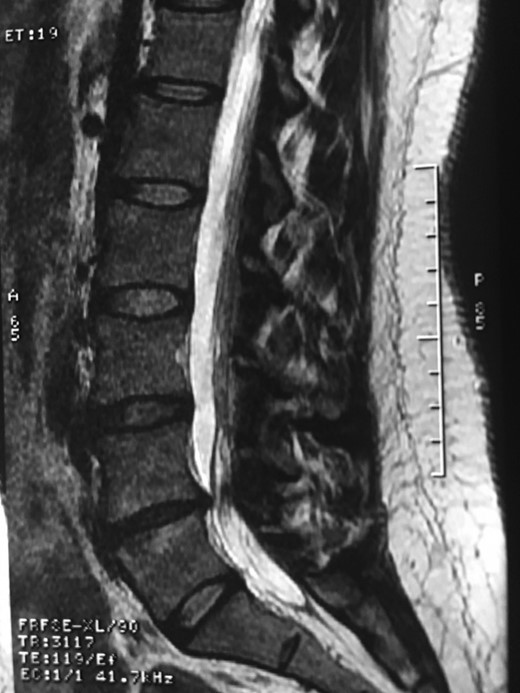

A 42-year-old female presented to the clinic with a history of chronic low back pain. She reported no relevant medical history. She had already been treated in the last 4 years by general practitioners with analgesics and home based physiotherapy with no satisfactory results. She had two previous admissions to the emergency department where morphine was prescribed to control the pain on her lower back. She was under ambulatory treatment with diclofenac, and tizanidine with partial relief of symptoms. Her main complaint was pain on the lower lumbar back with no radiation to the lower extremities. In her physical evaluation she presented limitation to full rotation and bending of the lumbar spine due to pain. Lasegue sign was negative, sensitivity, reflexes, sagittal balance, distal muscular strength and pulses were normal. Radiographs showed an overdeveloped left transverse process of the fifth lumbar vertebra which contacts with the sacrum at the left sacral wing with signs of degeneration at the same site (Fig. 1). Magnetic resonance imaging (MRI) studies were obtained (Figs 2–5). The patient was taken to the operating room where infiltration with 1 mL of lidocaine and 40 mg of Triamcinolone was performed in the pseudoarticulation between the left transverse process and the sacrum under fluoroscopic guidance. She reported a complete relief of pain after the procedure. At three months follow-up she was managed with strengthening and stabilizing exercises for the lumbar spine and postural education was initiated. She remains asymptomatic at her 12 months follow up.

Degenerative changes at the facets and disc in the adjacent segment.

The partial fusion at the lower part of the lumbosacral transition produces important alterations in normal biomechanics at the levels immediately above and below the LSTV. Changes such as hypermobility and abnormal torque moments are present at the level above the LSTV, predisposing it to early degeneration (early disc pathology and facet joint degenerative disease). Restricted movement below the LSTV produces a protective effect against degeneration of disc and facets and is related to changes (facets are smaller and coronally oriented) in the dimensions of the lower level facet joints [7]. These alterations can be verified in the adjacent levels of the LSTV in our patient.